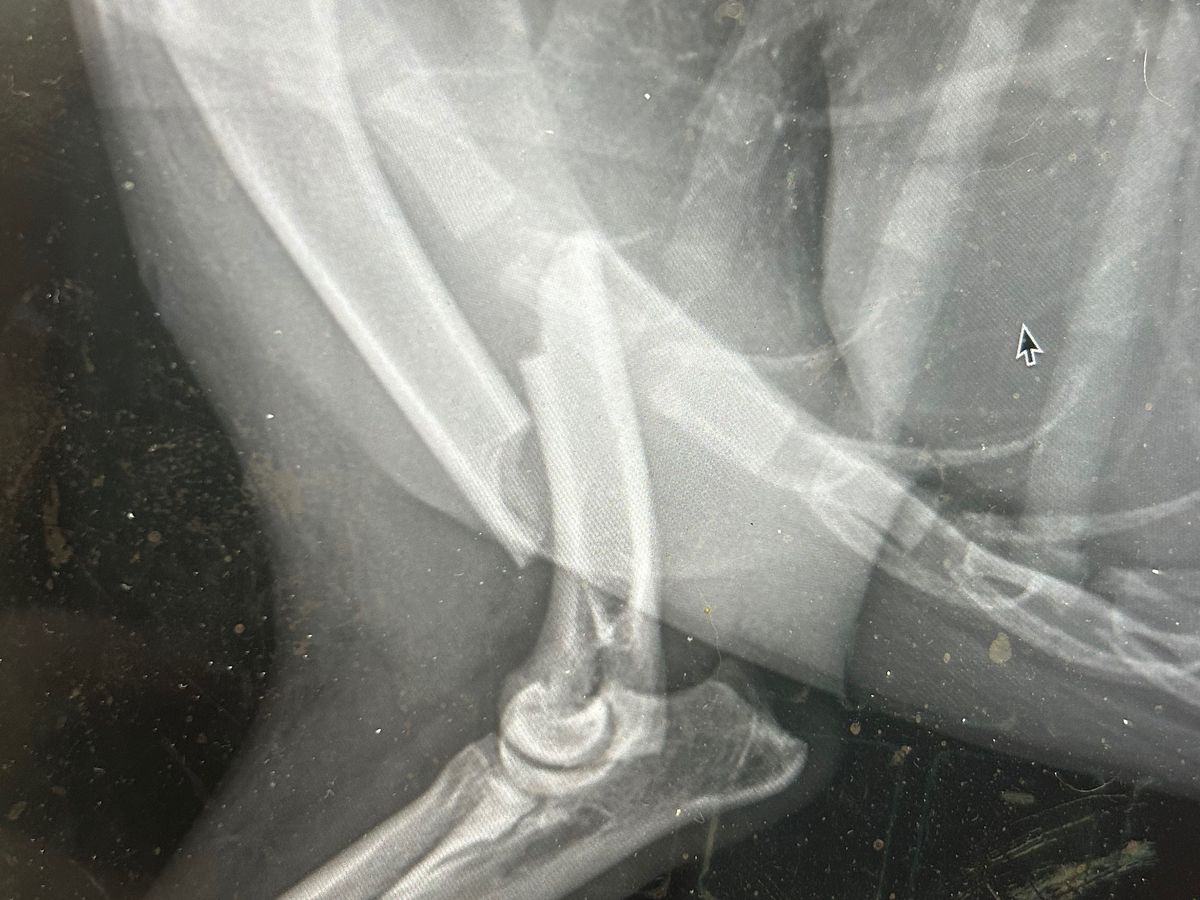

Yesterday, one of our pups, Cali, that we are working to adopt to her forever home, was kicked by a horse. She has a very clean but severe break in her shoulder and will require surgery! However, this surgery is approximately $6000, possibly more depending on the severity of the surgery, and there is no denying it, we just don't have it.